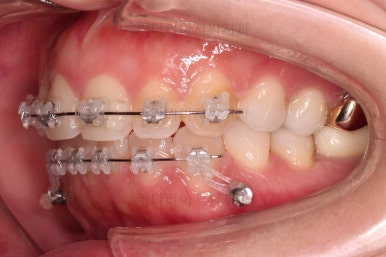

이번에 부산부분치아교정 환자분이 선택하신 장치는 엠파워 클리어라고 하는 자가결찰 세라믹인데요.

흔히들 아시는 클리피씨가 이러한 종류의 장치에요.

아랫니는 일반 브라켓 보다 매우 작은 장치가 들어갔는데요.

미니튜브 장치에요.

그래서 초기 정렬단계에서는 미니튜브를 이용해 주고, 추후에 좀 더 정교한 조절이 필요한 상황에서는 브라켓장치(엠파워 클리어)로 재부착하기로 했어요.

장치 부착 직후의 얼굴 모습인데요.

입이 얼마나 나오는지에, 웃을 때 보이는 브라켓의 모습은 어떤지 참고해 주세요.

이번 환자분은 브라켓을 부착했다고 해서 입이 거의 나오지 않는 경우였어요.

이처럼 입이 얼마나 나올지는 사람마다 매우 달라서 일단 붙여봐야 아는 경우가 많답니다.